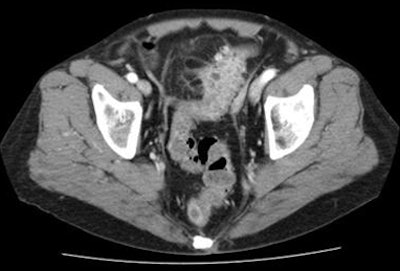

![]() |

| Diverticular disease above reveals wall thickening and stranding in the pericolonic fatty tissue at CT. Case below shows moderate obstruction and acute inflammation. Both are classified as stage 0 by the Hanson/Stock method and as stage I by the modified Hinchey method. |